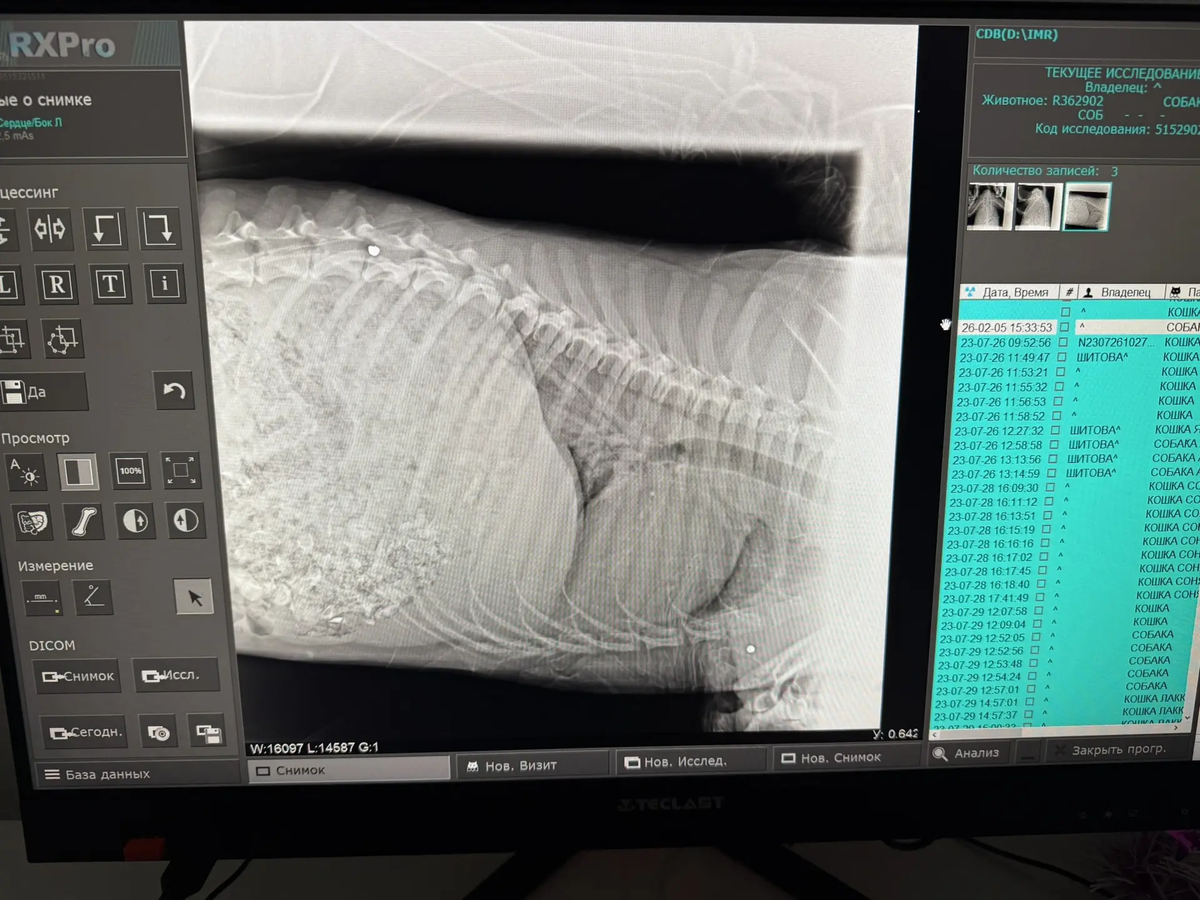

У собачки сохранена чувствительность в лапках, но сами задние лапы уже стёрты и в ранах. Мы сделали рентген (оставались денежки с оплаты аренды) и были в шоке. В очередной раз перед нами собака, в которую стреляли ИЗ ДРОБИ! Таз, брюшко — ВСЁ В ПУЛЯХ! Перелом таза…

А ещё, похоже, ПНЕВМОНИЯ! Нужен кардиолог, травматолог. Нужно сдать кровь обязательно — общий и биохимию, ПЦР. Также у собачки полный желудок КОСТЕЙ.